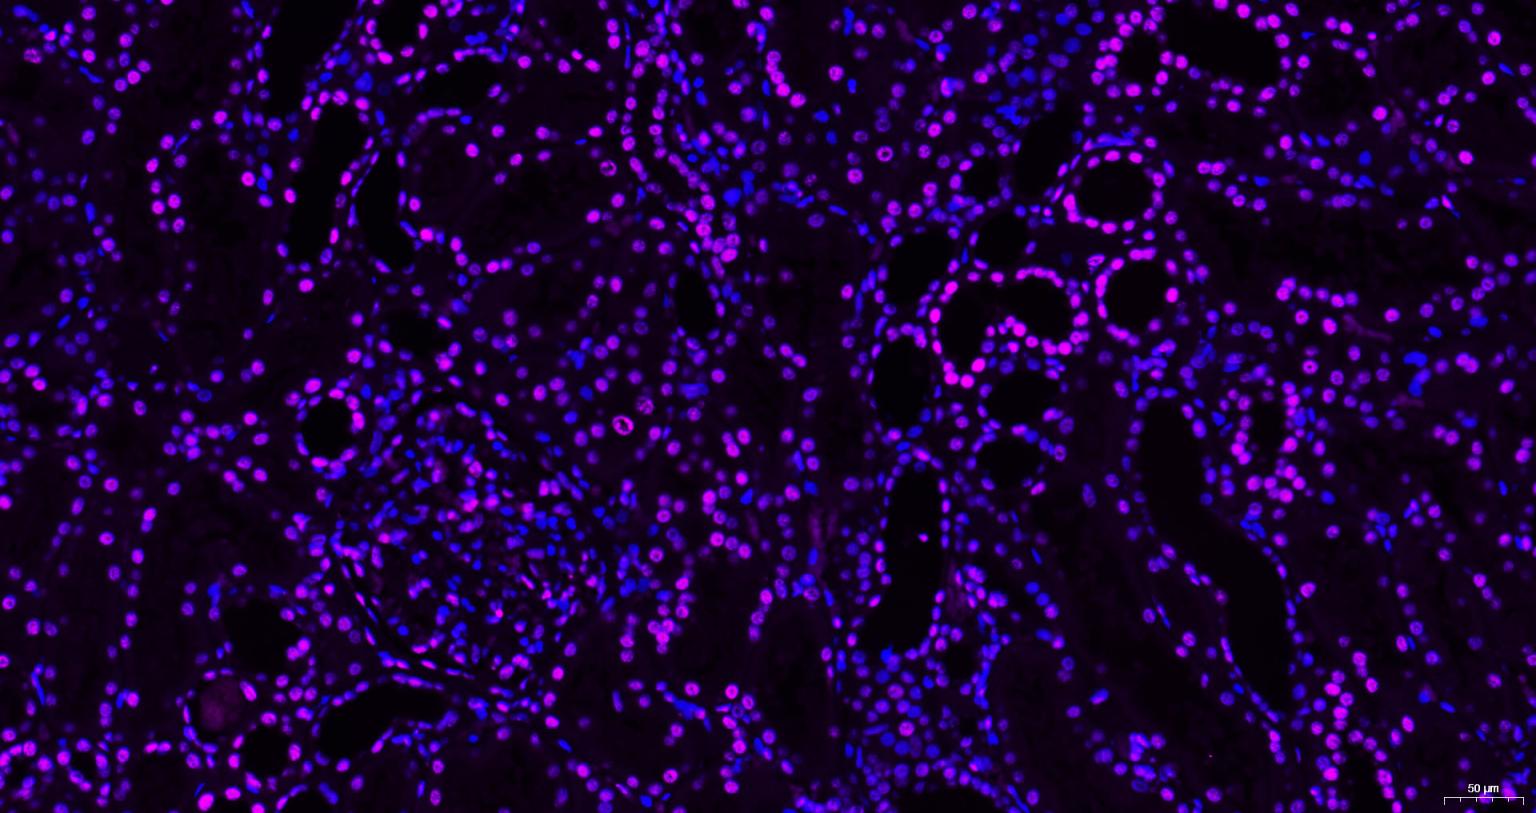

Paraformaldehyde-fixed, paraffin embedded Human Kidney; Antigen retrieval by boiling in sodium citrate buffer (pH6.0) for 15 min; Antibody incubation with Histone H3 Monoclonal Antibody, Unconjugated (bsm-33042M) at 1:200 overnight at 4°C. Followed by conjugated Goat Anti-Mouse IgG antibody (Purple, bs-0296G-Cy5), DAPI (blue, C02-04002) was used to stain the cell nuclei.